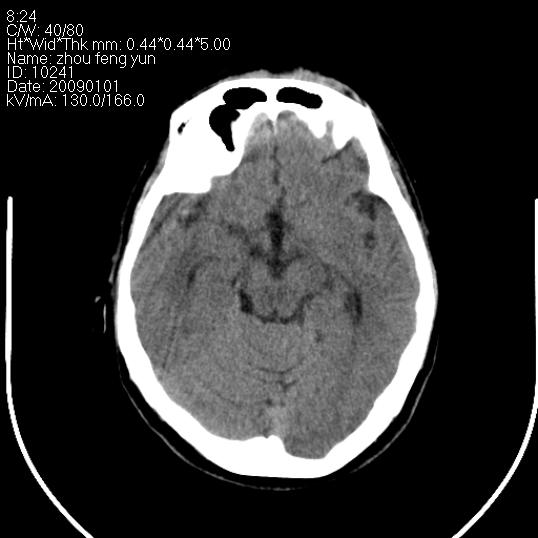

以下是引用hhcckk在2009-1-1 16:39:00的发言:[br]胼胝体嘴、膝部及部分体部发育不全,为囊状影替代,两侧侧脑室分离,脑室后角扩张[br][br]诊断:胼胝体发育不良[br][br]胼胝体发育不良(dysgenesis of the corpus callosum)是最常见的颅脑畸形,是胚胎期背部中线结构发育不良的一种形式。主要包括胼胝体缺如和部分缺如。胼胝体发育不良还可合并其他畸形,如胼胝体脂肪瘤、蛛网膜囊肿、脑膨出、chiari畸形、灰质异位症、脑回畸形等。[br][br]ct诊断要点:[br]1. ct横断扫描可见两侧侧脑室明显分离,脑室后角扩张,形成典型的蝙蝠翼状侧脑室外形。[br]2. 第三脑室扩大并向上插入两侧脑室体部之间,严重者第三脑室可上移到两侧大脑半球纵裂的顶部。在ct冠状扫描位显示更清。[br]4. 胼胝体畸形常伴有脂肪瘤,可测到其特征性脂肪密度。部分脂肪瘤的边缘可出现线样钙化[br]